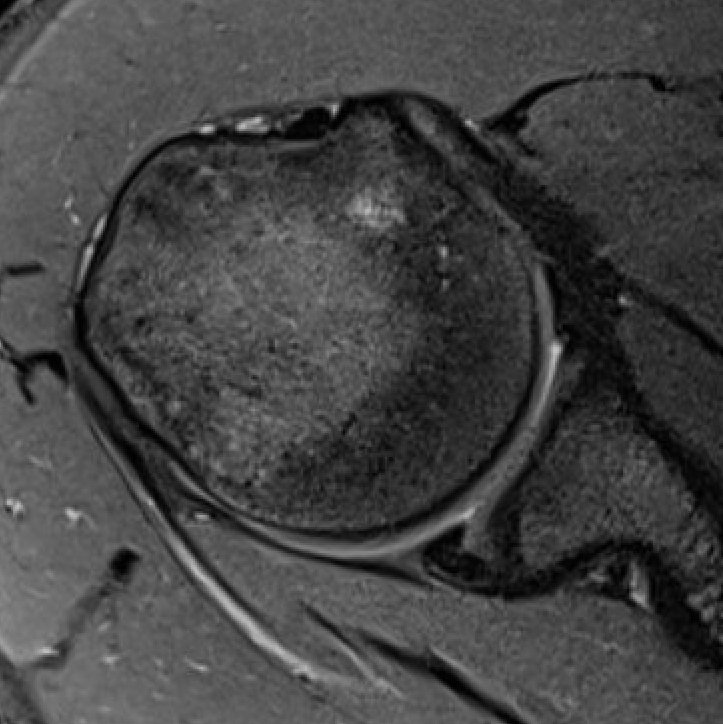

MRI

Posterior labral tears / bankart lesion

Posterior labral tear

Posterior labral tear

Posterior labral tears + cyst

Posterior glenoid wear / osteoarthritis

Beware early posterior glenoid OA presenting as posterior labral tear